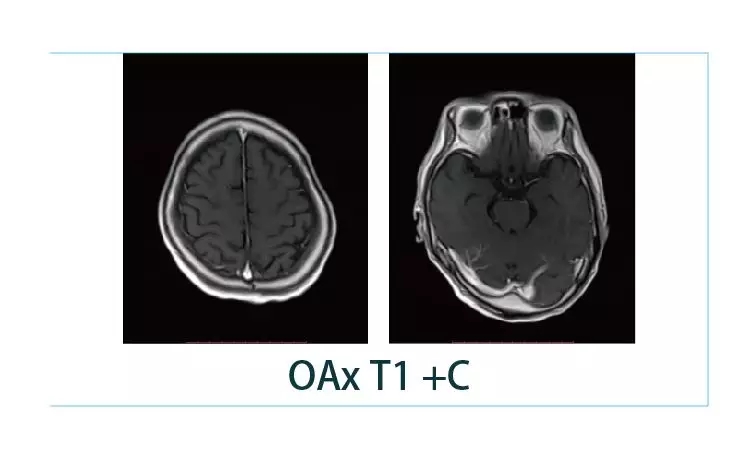

【朗润影像档案】20190125磁共振影像病例结果讨论